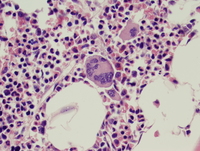

Aspirate

The atypical megakaryocytes are evident on the aspirate smear, including quite large forms with abundant cytoplasm, and deeply lobulated nuclei.